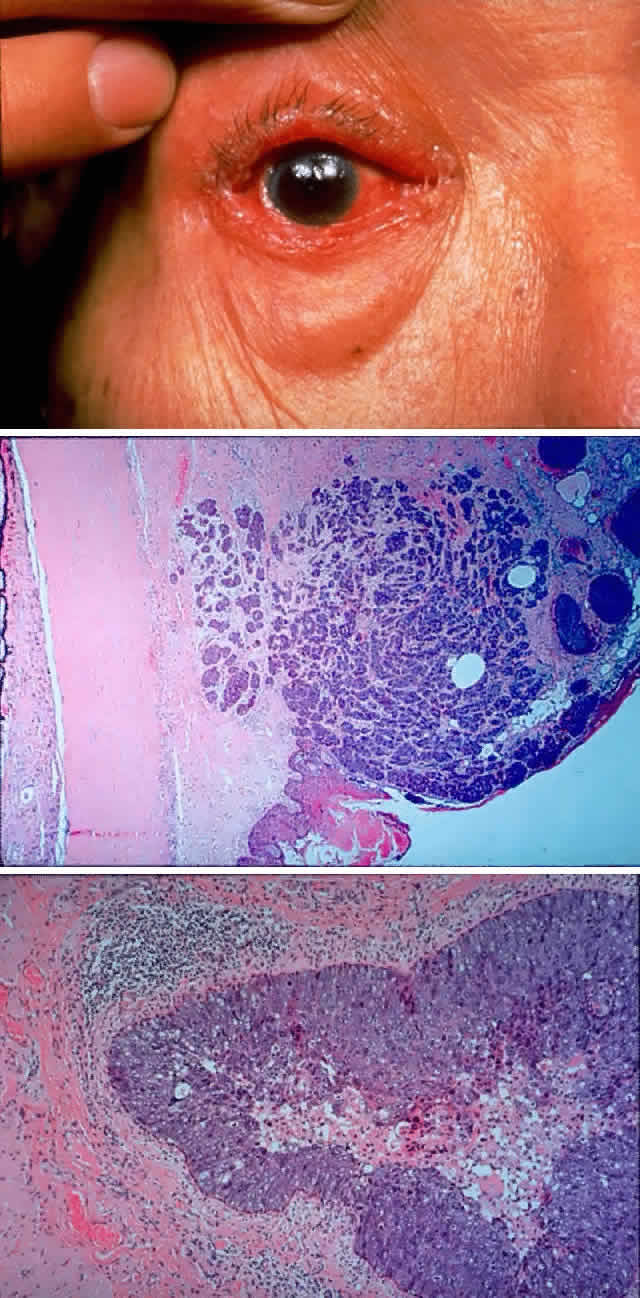

Sebaceous carcinoma has achieved a notorious reputation because it can be difficult to diagnose correctly in the early stages. Clinically, the tumor may masquerade as a chronic chalazion, blepharoconjunctivitis, basal cell carcinoma, keratoconjunctivitis, or very rarely as a primary orbital tumor. Another cause for confusion has been pathologic misdiagnosis of sebaceous carcinoma, most commonly being mistaken for basal cell carcinoma or squamous cell carcinoma. Increasing awareness of the characteristic presentation, along with earlier and more accurate clinical and pathologic diagnosis, has decreased the mortality associated with this tumor. The blepharoconjunctivitis associated with this lesion is the result of intraepithelial (pagetoid) spread of sebaceous carcinoma. The usual clinical appearance is a thickening of the conjunctiva associated with frank injection in areas of invasion (Fig. 9). A careful biomicroscopic examination reveals yellowish, plaque-like foci within the affected epithelium.

Fig. 9. A 79-year-old man had been treated for several years for chronic blepharoconjunctivitis. On examination, he had thickening of upper and lower lid margins, diffuse symblepharon, conjunctival thickening, injection, and yellowish plaque-like foci (A). Conjunctival biopsy confirmed invasive sebaceous cell carcinoma, and subtotal exenteration was performed. Tumor invasion along the globe (B) (H & E, × 32) and into muscle (C) (H & E, × 80) was noted.